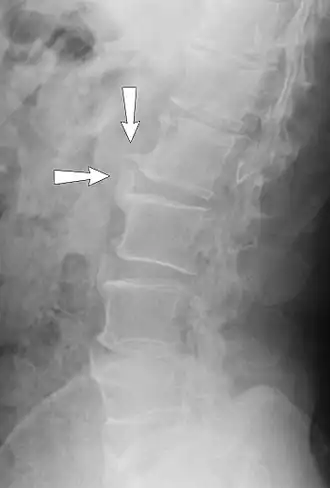

КТ спондилёза, вызывающего радикулопатию

Спондилёз (spondylosis; греч. «spondylos»- позвонок; син. деформирующий спондилёз) — инволюционный процесс постепенного изнашивания и старения анатомических структур позвоночника, сопровождающийся дистрофией наружных волокон передних или боковых отделов фиброзного кольца, выпячиванием его под давлением сохранившего свой тургор мякотного ядра, отложением и оссификацией передней продольной связки и образованием краевых костных разрастаний (остеофитов) вдоль оси позвоночника только по окружности передних и боковых отделов.

При спондилёзе костная ткань суставов разрастается, образуются остеофиты, то есть дополнительная костная ткань (по мере нарастания костный вырост распространяется к соседнему позвонку, тогда как от соседнего позвонка образуется такой же вырост, в некоторых случаях окостенение начинается на уровне межпозвоночного диска). В особо тяжёлых случаях наступает сращение позвонков, от чего страдают сосуды, нервы и мышечная ткань, а также близлежащие органы.